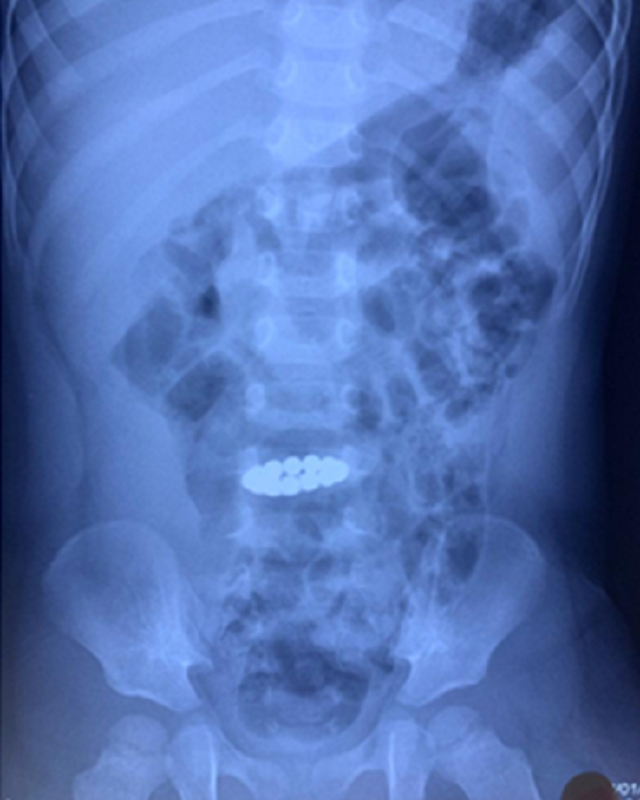

| Chuỗi nam châm hít vào nhau được phát hiện trên hình ảnh X-quang bụng của bệnh nhi |

Tuy nhiên, một tháng sau trẻ đột nhiên bị đau bụng, tình trạng diễn tiến nặng phải chuyển đến Bệnh viện Nhi Đồng Thành Phố cấp cứu. Các bác sĩ đã kiểm tra hình ảnh và phát hiện dị vật còn trong đường ruột của bệnh nhi và hít vào nhau xếp thành hình vòng tròn.